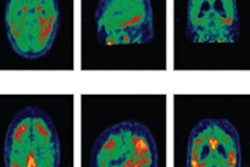

The PET images revealed no significant differences between the super-agers and the younger control group in terms of in vivo tau and amyloid burden. The normal-agers group exhibited tau burden in inferior temporal and precuneal areas but no significant differences in amyloid burden when compared with the controls. Patients with mild cognitive impairment showed both high amyloid and high tau pathology burden.

Tau (blue) and amyloid (orange) distribution patterns for super-agers, normal-agers, and MCI patients, who were compared to a group of younger, healthy, cognitively normal, amyloid-negative individuals. Brain projections are depicted at an uncorrected significance (p < 0.0001). Color bars represent the respective t-statistic. Images courtesy of SNMMI and Hoenig et al.The cognitive prowess of the super-agers "appears to be associated with the resistance to tau and amyloid pathology, which likely permits maintenance of cognitive performance despite advanced age," Hoenig and colleagues concluded. "In turn, differences between normal aging and mild cognitive impairment appear to be driven by the level of amyloid burden. These results motivate further research to determine responsible resistance factors, which may also inspire the development of novel treatment concepts."